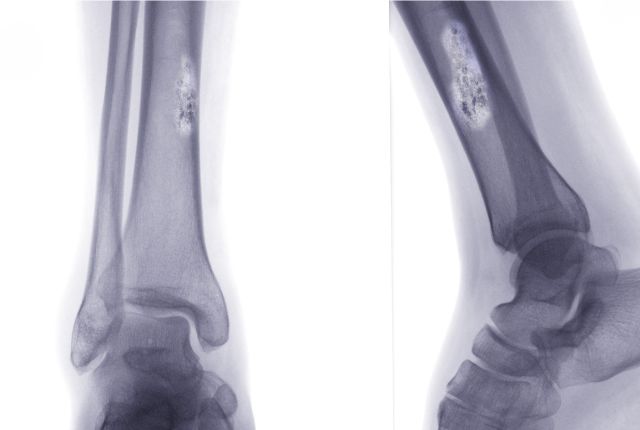

Radiographie

La radiographie permet de déceler des anomalies au niveau des os, une excroissance, voire un trou. Il est difficile néanmoins de conclure avec cet examen si la tumeur décelée est cancéreuse ou non. Dans certains cas, il permet néanmoins d'écarter le diagnostic de cancer comme dans la maladie de Paget.

L' ostéosarcome touche généralement les os du tibia et du fémur (os longs), mais aussi le genou. Cette tumeur rare et agressive touche souvent les jeunes hommes.

Tibia, jambes, genoux

Le cancer des os touche souvent le tibia, le fémur, les genoux, le bassin, les jambes, ou les cartilages. Ces zone sont concernées par les trois formes de cancer des os les plus fréquentes : ostéosarcome, sarcome d'Ewing et chondrosarcome.